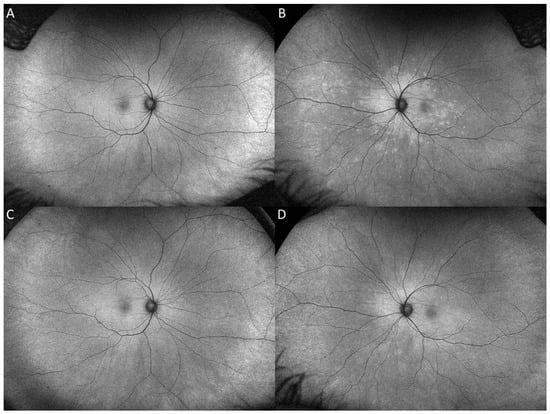

2. Case Report